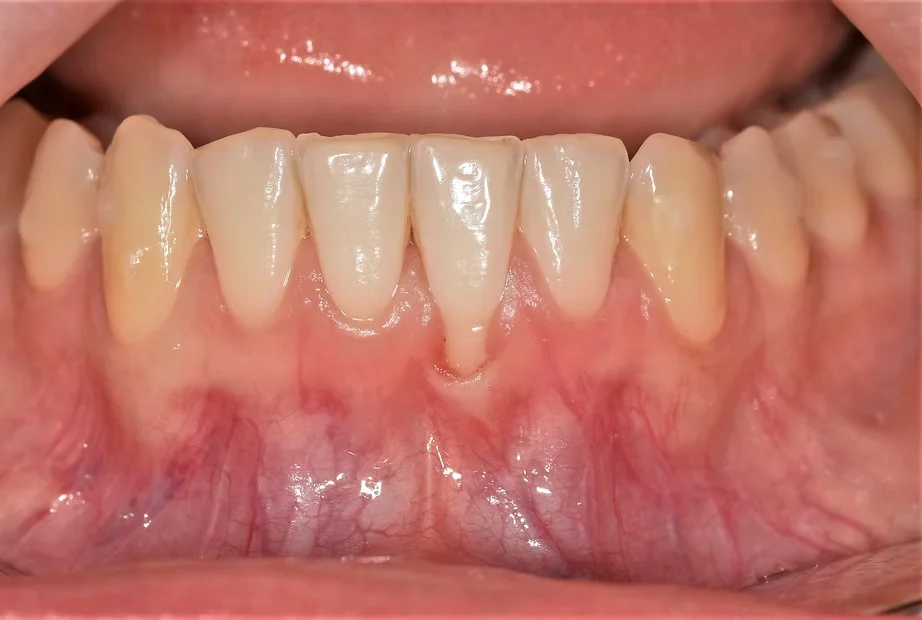

• Gencives rouges, gonflées ou sensibles

• Récession gingivale